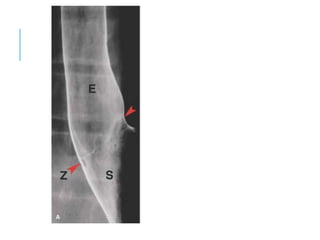

Z-LINE SQUAMOCOLUMNAR

JUNCTION

Z- Line